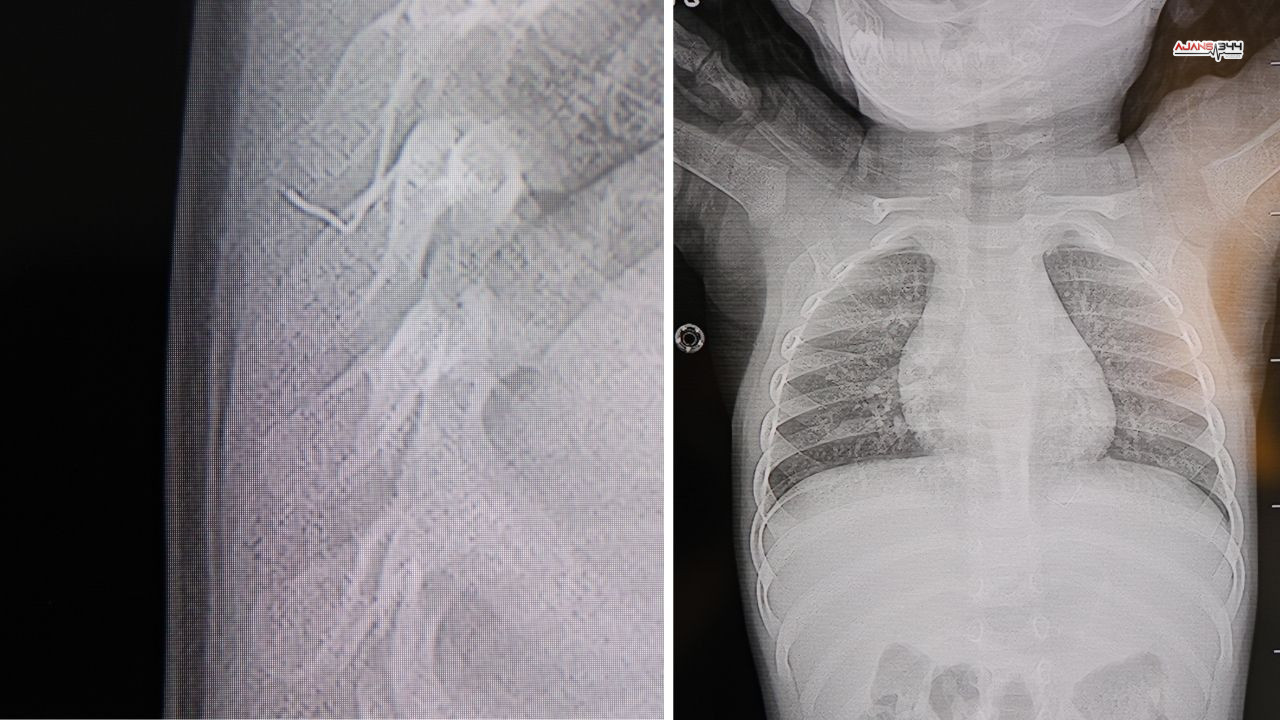

HG Hospital’de yapılan incelemelerde, Prof. Dr. İdris Altun tarafından yabancı cismin cilt altında, omurilik kanalına oldukça yakın bir noktada bulunduğu ve akciğer zarına doğru ilerlediği tespit edildi. Yapılan değerlendirme sonucunda beklemenin ciddi sağlık riskleri doğurabileceği kanaatine varıldı.

Bebek, genel anestezi uygulanmadan, lokal anestezi ve sedasyon eşliğinde ameliyata alındı. Gerçekleştirilen cerrahi müdahalede yabancı cisim tamamen çıkarıldı. Operasyon sırasında çıkarılan cismin, yaklaşık 2 santimetre uzunluğunda, ince zımba teline benzer metal bir tel olduğu belirlendi. Müdahale sonrası herhangi bir komplikasyon gelişmedi.